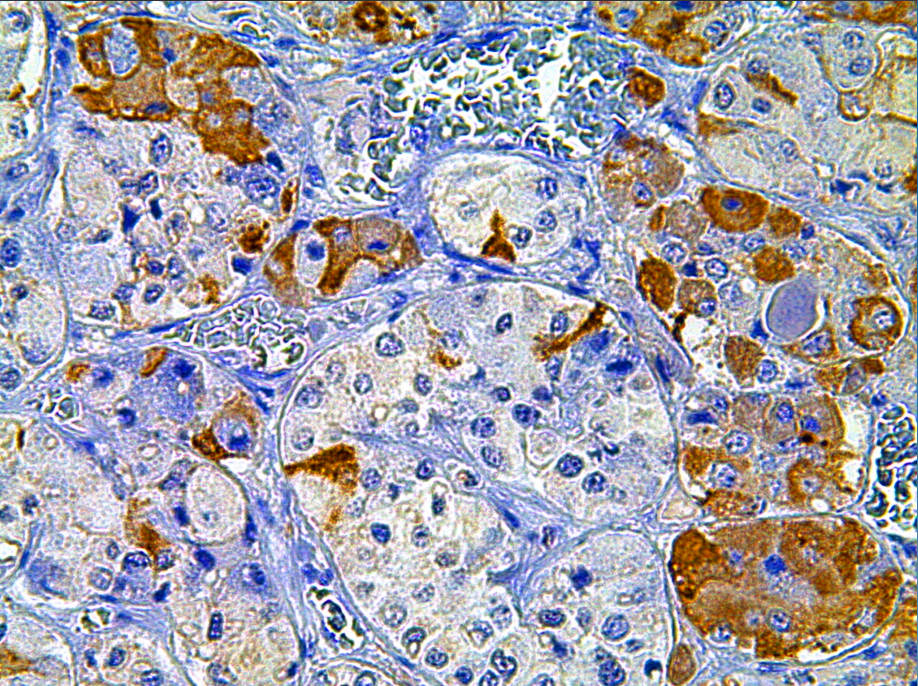

Positive control: Pituitary gland

Luteinizing hormone is a hormone secreted by pituitary cells. This antibody reacts with human luteinizing hormone and has a weak cross-reaction with thyroid stimulating hormone, follicle-stimulating hormone or human chorionic gonadotropin. It is mainly used in the research of functional classification of pituitary adenomas.

LH antibody reagents can specifically bind to LH antigens. Immunohistochemical kits containing LH antibody reagents are suitable for the typing of pituitary adenomas.